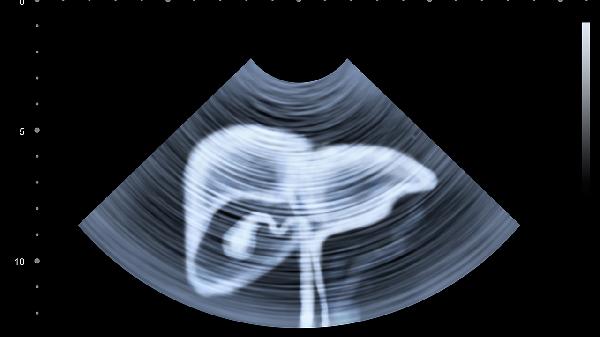

日常应注意记录疼痛发作时间与诱因,避免剧烈运动和腹部受凉。饮食选择易消化的粥类、蒸煮食物,限制辛辣刺激及产气食品。若疼痛持续超过6小时、出现发热或便血等警报症状,须立即急诊处理。建议完善血常规、超声或CT等检查明确病因,不可自行服用止痛药掩盖病情。